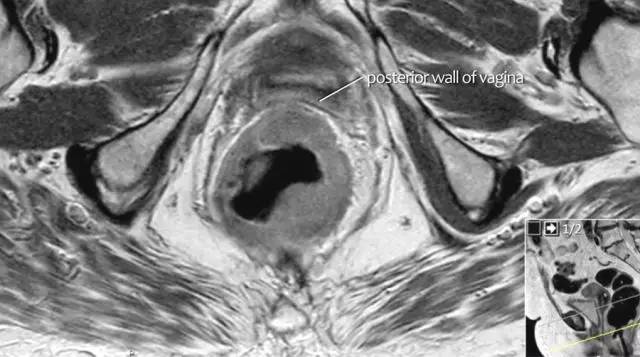

图 16 在矢状 T2W 图像上,直肠和阴道后壁之间有脂肪平面的损失。在轴向图像上,看到肿瘤的相对低的信号强度延伸到阴道的后壁(箭头)

以下 5 幅图例请连续观看:

图 17~21 肿瘤的低信号强度延伸到阴道的后壁(箭头)